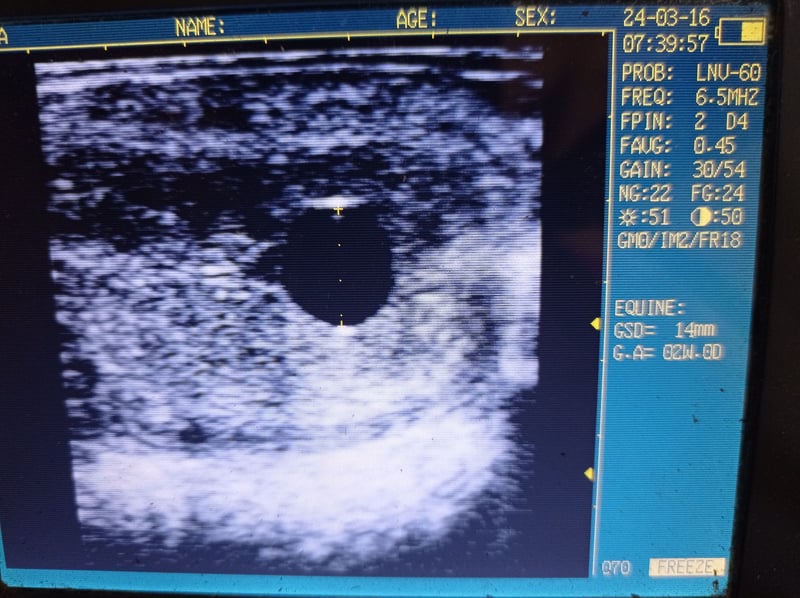

Pedigree and ultrasound picture in the pictures.

Parida para 2025 por el Holsteiner Roxett (Ramiro x Corde la Bryere)

Pedigree y imagen de ultrasonido en las fotos.

Ascendance et échographie avec les photos.

Pedigree e foto ecografica con le immagini.

Stamboom en echo in de foto's.

Rodowód i zdjęcie USG na zdjęciach.

Stamtavla och ultraljudsbild i bilderna.